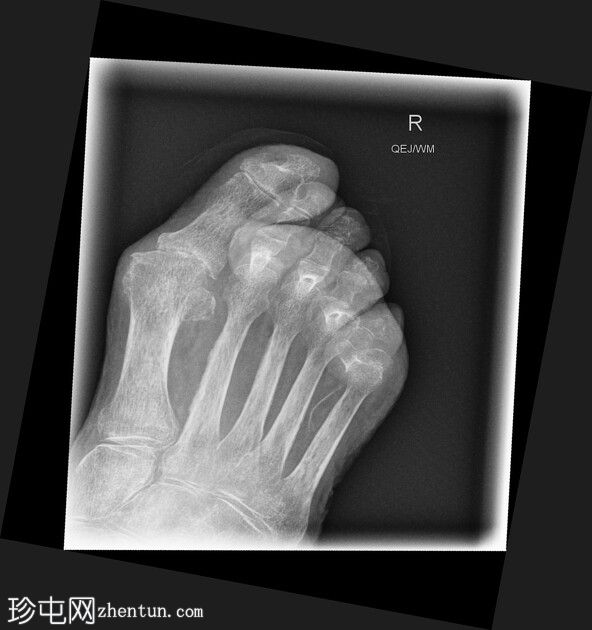

正位

斜位

第二至第五趾跖趾关节明显过伸,近端趾间关节屈曲,符合爪状趾畸形。部分远端趾间关节屈曲程度不及其他关节。